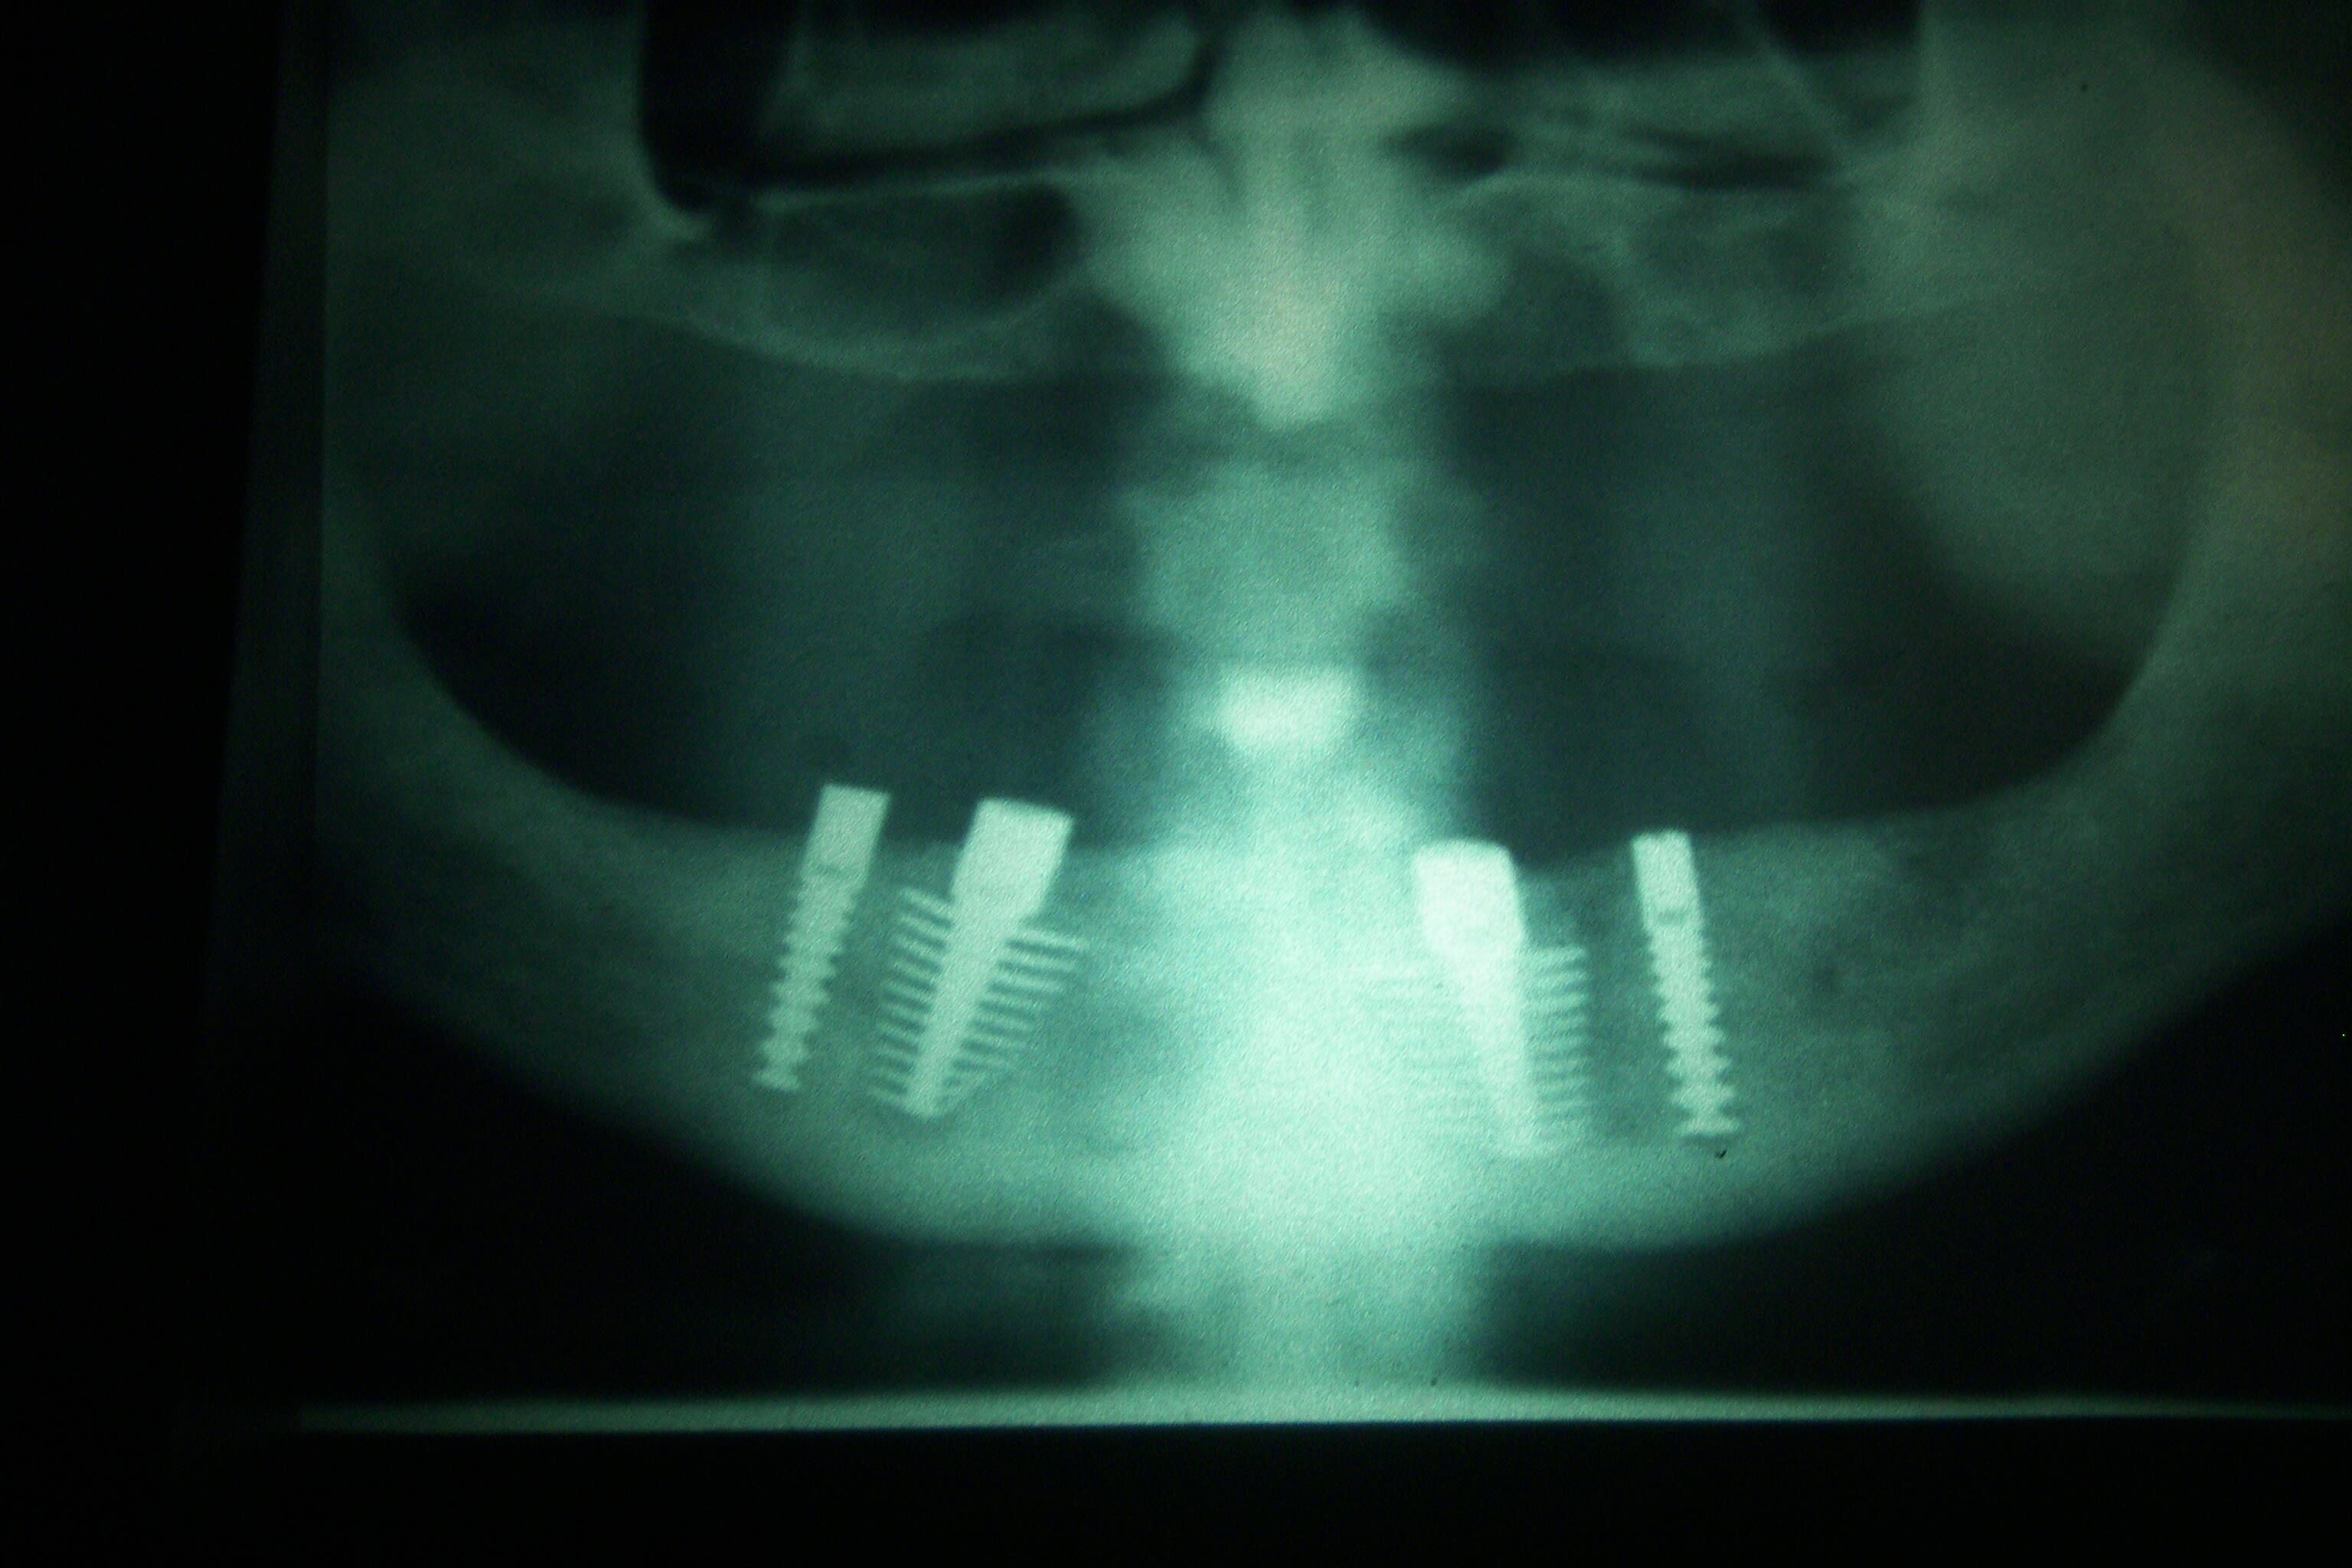

De la pano la moins marrante Ă  la plus marrante :

Regarde moi ça 4 Implants et on va jusqu'aux 7 voir jusqu'aux 8 sans problùme 😊